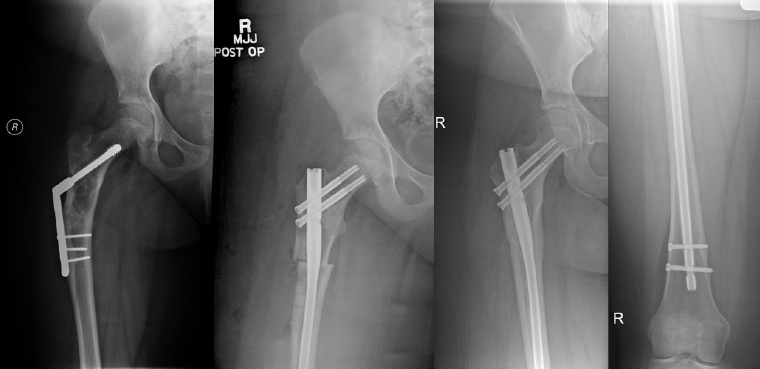

Complications occurred in 5 patients with tibial DC, including 3 cases of hardware removal due to symptomatic prominent interlocking screws and 1 case of delayed union. Complications arose in 4 patients with femoral DC, including 3 cases of nonunion, 1 case of hardware removal due to prominent screws, and 1 case of nonunion and infection (Table 1). There were no cases of peroneal nerve palsy or compartment syndrome. All patients achieved eventual clinical and radiographic union. Pre- and postoperative radiographs of 4 cases are included to highlight the variation in presentation and operative site (Figs. 4-7).

From left to right: Preoperatively, immediately postoperatively, and 4 years postoperatively (patient #4).